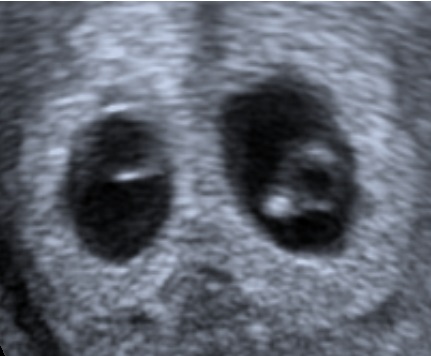

In twin pregnancies prenatal diagnosis of chorionicity is important because chorionicity rather than zygocity is the main factor determining pregnancy outcome. An important feature of dichorionicity is the extension of placental tissue into the base of the inter-twin membrane. This sign has been named the Lambda sign and is typically used at 10-14 weeks (Sepulveda et al., 1996).